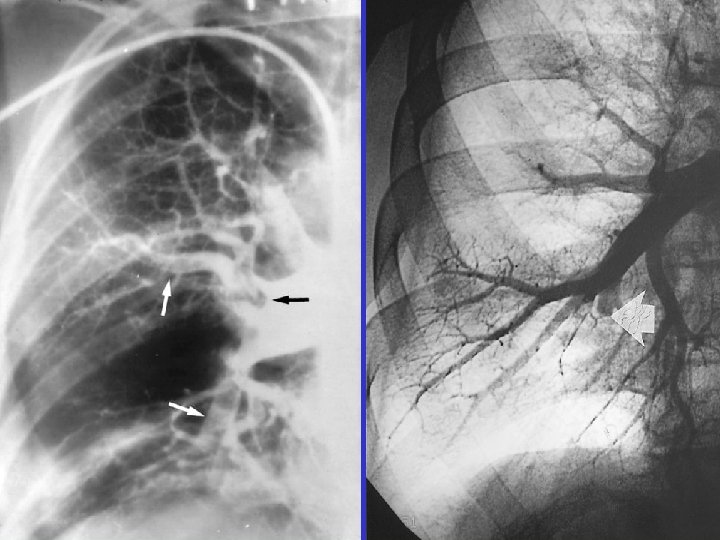

Angiography

Angiography: massive PE Acute: 45/20 mm. Hg Subacute: 85/50 mm. Hg

CTPH m. PAP = 75 mm. Hg